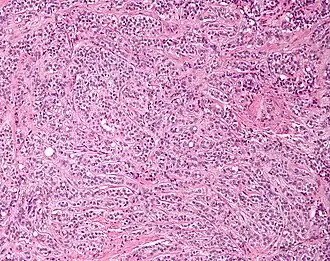

Micrograph of a Leydig cell tumour

Micrograph of a Leydig cell tumour -